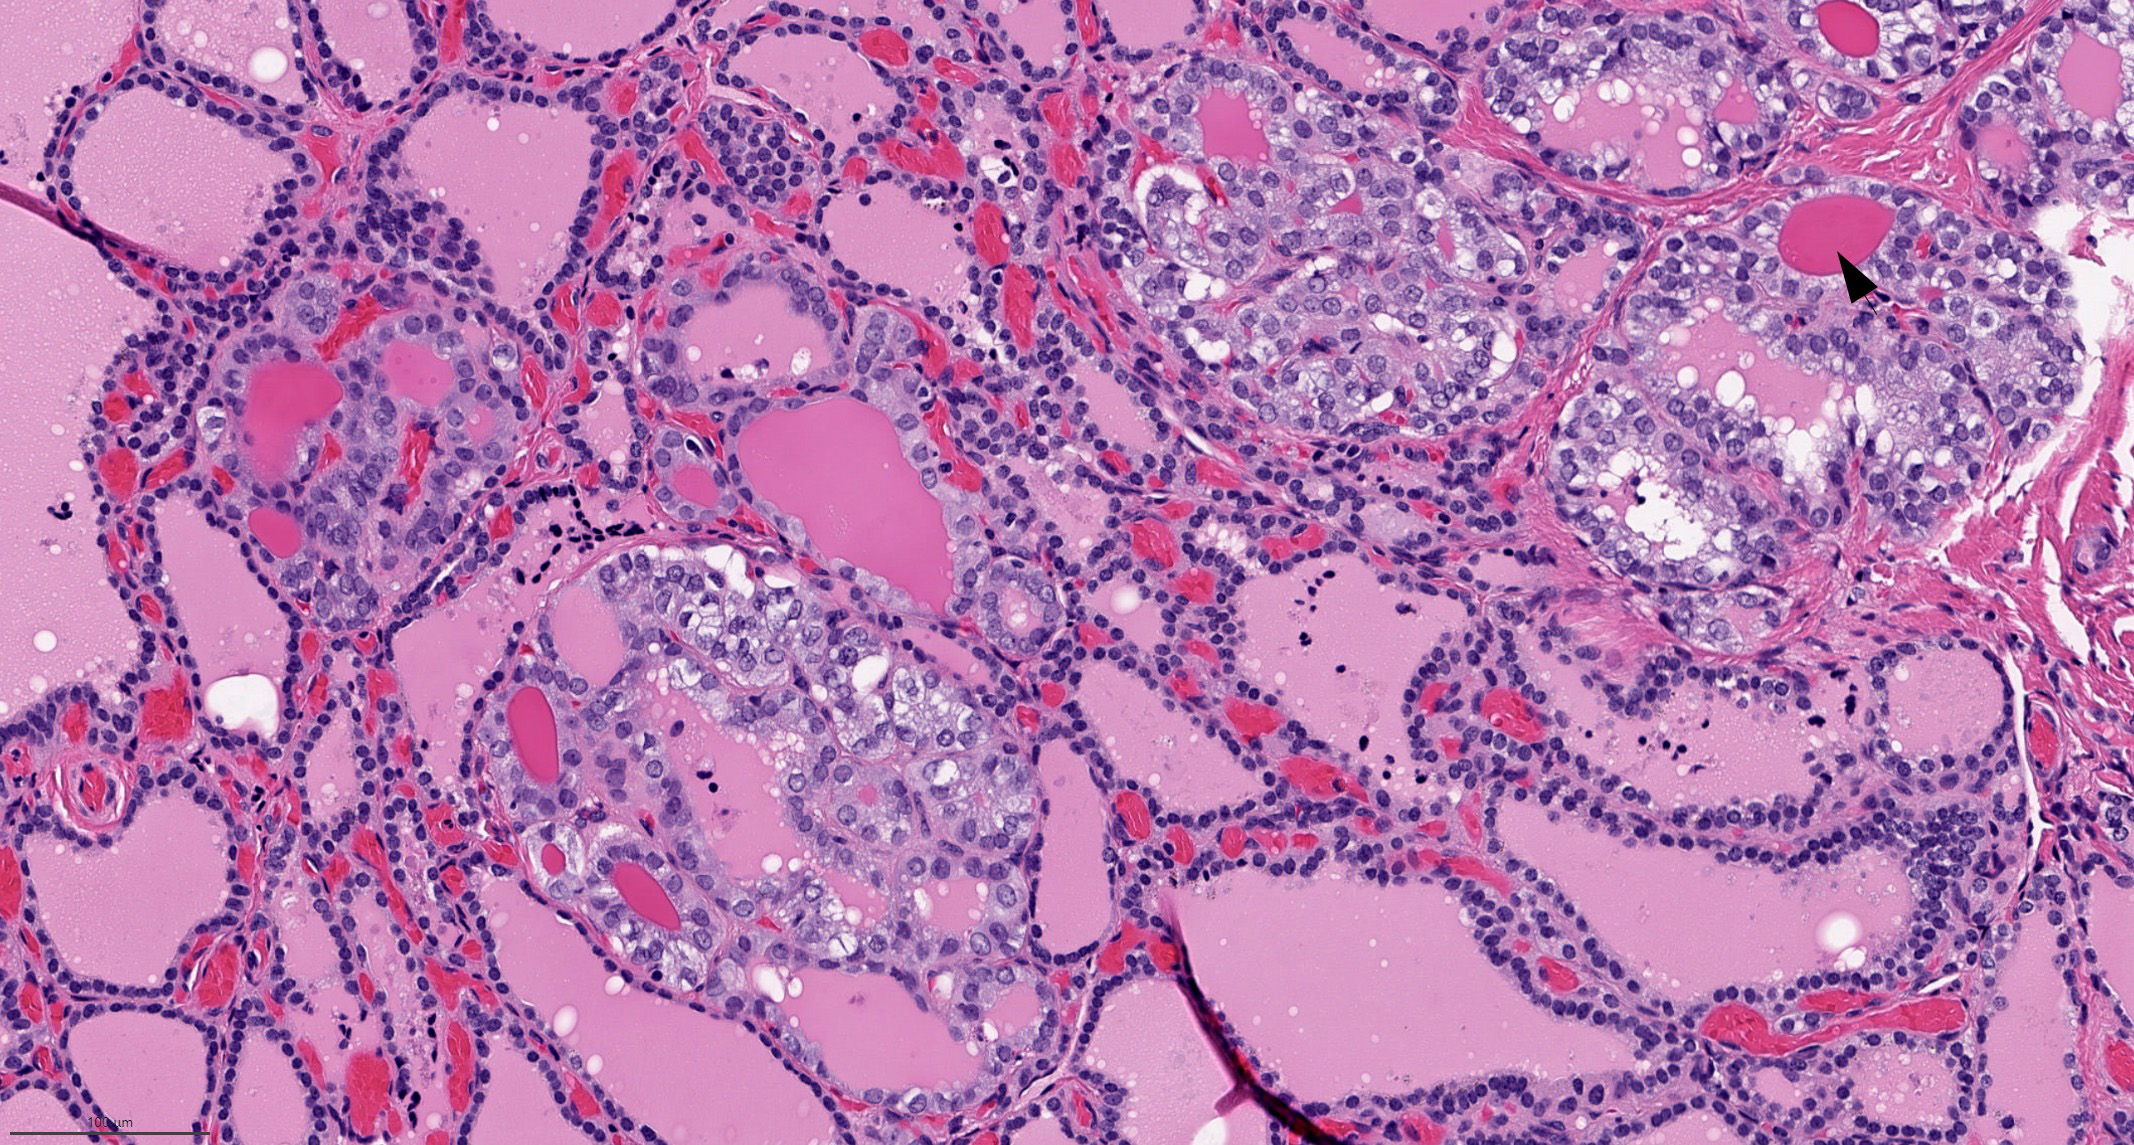

Microscopic (histologic) description

- Nuclear features of papillary thyroid carcinoma should be seen multifocally (at least 2 foci) or diffusely within the tumor; such features include nuclear enlargement, nuclear overlapping, chromatin clearing, nuclear membrane irregularity and nuclear grooves (J Clin Endocrinol Metab 2017;102:15)

- Architecture: exclusively or nearly exclusively follicular

- True papillae with fibrovascular core are in general absent in follicular variant

- Encapsulated follicular variant has a complete fibrous tumor capsule or a well circumscribed tumor border

- "Bubble gum colloid", i.e. dense homogenous hypereosinophilic colloid, may be seen in the lumen of neoplastic follicles; scalloping of colloid may be seen

- Psammoma bodies are exceedingly rare in follicular variant; the identification of psammoma body should promote a search for true papillary (classic) area within the tumor

Microscopic (histologic) images